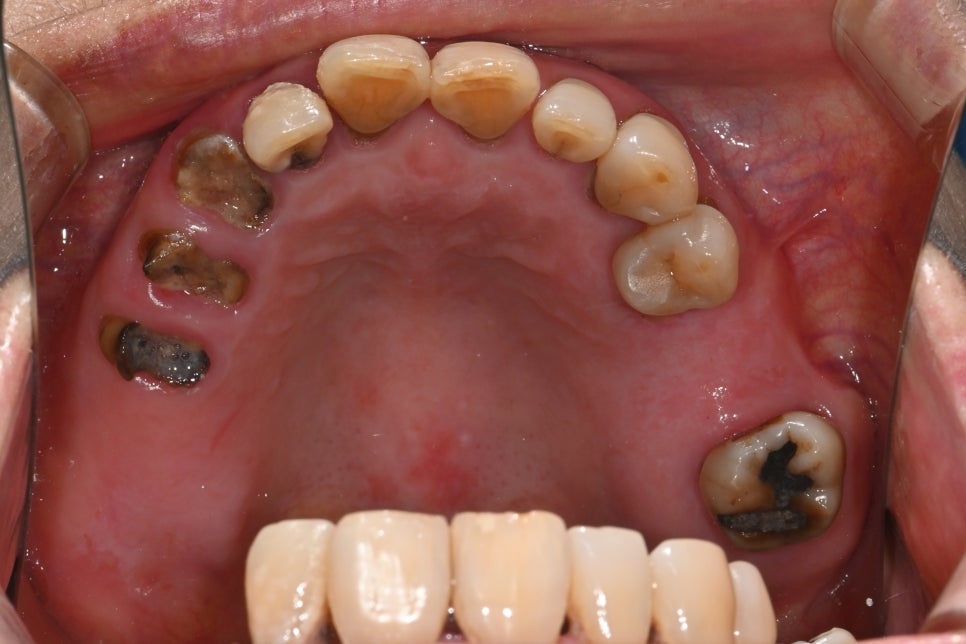

환자분은 30년 이상 치과 진료를 미루며

전체적인 치아 마모, 탈락, 잇몸 염증이

복합적으로 진행된 상태였습니다.

특히 어금니가 거의 모두 빠져 있어

저작 기능이 상실된 상황이었고

남아 있는 치아들도 마모가 심해 교합을

유지하기 어려웠습니다.

잇몸 사이에는 음식물이 끼면서

염증과 냄새가 반복적으로 발생했고

일상적인 식사에도 많은 불편이 있었습니다.